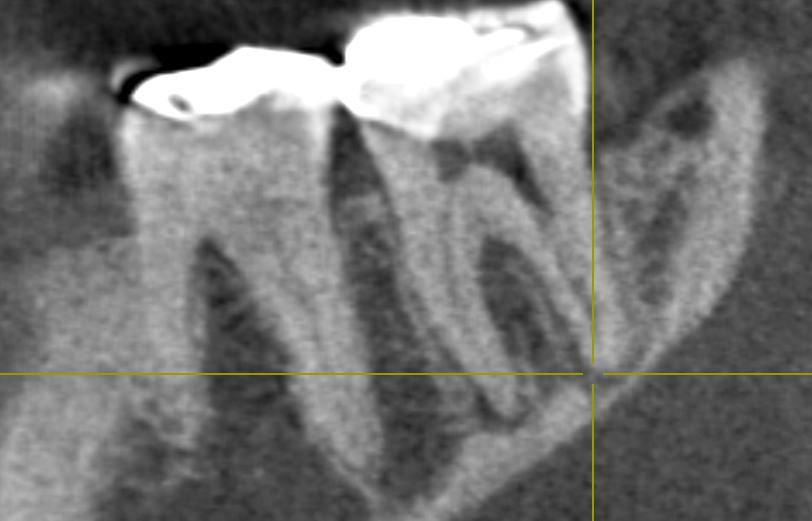

いつも通りまず歯科ドックをして原因を調べます。ドックの結果神経が死んでいました。しかし今回わからなかったのは分岐部といって歯の又の部分にも病変がありました。。。

CTとデンタルをみると髄床から何か管か破折線か見えます。なんだろう。これが分岐部病変の原因ではないかと思います。歯科ドックをしたからここまでわかりました。

ん?近心根の中に2根(珍しい)1つは分岐部へ。

非常に珍しいケース。近心の根管の中に分岐部があり根管がご覧の様に縦に並んでいました。根管の形態はご覧の様に様々。だから時間と精密さが求められます。